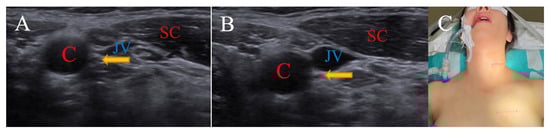

3.1.3. Neutral Position for Nervus Vagus

| SCM | Sternocleidomastoid |

| C | Carotid artery |

| JV | Jugular vein |